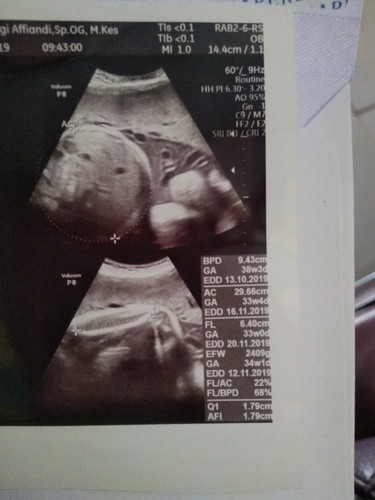

Alhamdulillah, posisi dedeknya sudah bagus. Hanya menunggu hari saja... Disini bunda bunda yang 38W3D HPL nya tanggal berapa ya? Kalau dokter ku matok di usia 10 bulan, jadinya perkiraan lahir maksimal 27 oktober bisa maju dari tgl itu yg penting gk lewat..